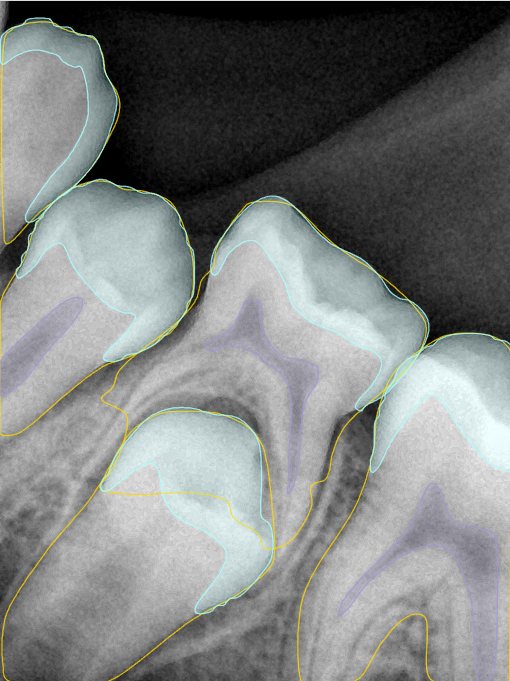

第二版算法问题测试

| 第一版 | 第二版 | 是否解决 | |

|---|---|---|---|

![]() | ![]() ![]() 边角识别有问题 龋齿识别不全 牙髓识别不全 | ![]() | 解决 |

![]() | ![]() 边角识别有问题 识别信息有误 自查(牙冠识别不全) | ![]() | 解决 |

![]() | ![]() ![]() 边角识别有误 大范围填充识别遗漏 | ![]() | 解决 |

![]() | ![]() 识别信息不全 | ![]() | 解决 |

![]() | ![]() ![]() 边角问题 牙胶识别不全 牙冠识别不全 | ![]() | 解决 |

![]() 换图片 | ![]() | ![]() 牙冠部分稍微白了一些就识别成小范围修补,部分判断异常 | 部分解决,修复类略敏感,牙冠部分稍微白了一些就识别成小范围修补,部分判断异常。 |

![]() | ![]() ![]() 牙冠识别不全 牙髓不全 根尖炎龋齿识别有误 | ![]() | 解决 |

![]() | ![]() | ![]() | 解决 |

![]() 换图片 | ![]() | ![]() | 解决 |

![]() | ![]() 牙冠识别有误 | ![]() | 解决 |

![]() 换图片 | ![]() ![]() 边角识别有误 | ![]() 修复类敏感 | 部分解决,图像过白,导致修复类判断异常。 |

![]() 换图片 | ![]() 牙冠识别不全 | ![]() 修复类敏感 | 部分解决,图像过白,导致修复类判断异常 |

结论:修复类出现了不鲁棒的情况,后续需要加入轮廓的扩充数据进行增强。